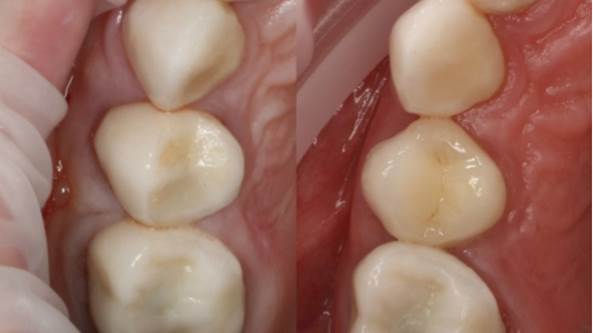

Clinical case: Digital Data Save concept in upper jaw premolar area

- Courtesy of Dr. Lysov Alexander Dmitrievich & Dr. Sofronov Matvey Vitalievich, Russia -

AnyRidge, R2GATE, R2GATE guide, ISQ value, initial stability, immediate loading, KnifeThread, maxillary posterior, #14, Digital, Dr. Lysov Alexander Dmitrievich, Dr. Sofronov Matvey Vitalievich, zirconia abutment, CAD/CAM crown

Products used

AnyRidge implant system, R2GATE, Digital prosthesis

“AnyRidge & R2GATE show stable results

after immediate extraction, immediate implant placement, & immediate loading,

even with low bone density.”